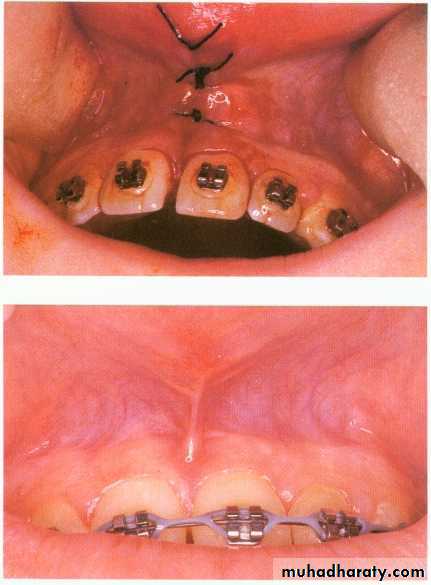

Frenectomy—the surgical removal of fraenal attachments (usually in the midline) in the upper or lower jaw—may be a valuable surgical adjunct to orthodontic therapy.

Labial frenectomy

Upper labial frenectomy aims to remove or reposition the entire labial frenum, including its attachment to bone, and to remove all interdental tissue. It must be remembered that spacing of the incisors in children is a normal developmental process and is present until the eruption of the permanent canine teeth in adolescents.Labial frenectomy should usually be delayed until after orthodontic treatment, unless the labial frenum prevents closure of a diastema or displays evidence of trauma. The technique is usually performed if the frenum extends to the incisive papilla and contributes to post-treatment stability of the orthodontically closed diastema.

Under local anesthesia the upper lip is firmly retracted, demonstrating the extent of the fraenal attachment. If the frenum is particularly fibrous, its whole length is outlined and excised with a scalpel using an elliptical or rhomboid incision. The remaining fibres attached to the exposed bone can be curetted or gently removed with a bur but care must be taken not to damage the roots of adjacent teeth. The mucosa is then undermined and the defect closed with simple interrupted sutures. Patients are normally reviewed in 5–7 days.Lingual frenectomy